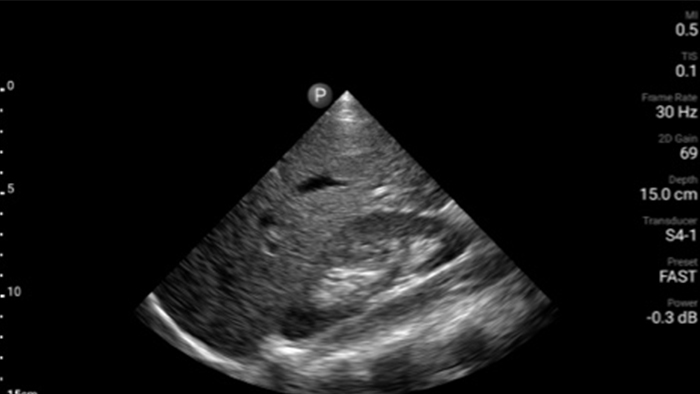

Lumify handheld ultrasound offers images that enhance diagnostic confidence.

See more when it counts

Lumify can help you make real-time decisions with more confidence, from assessment to recovery. Reveal the subtle details of an image, uncover enriched tissue definition with multiple angles and much more.